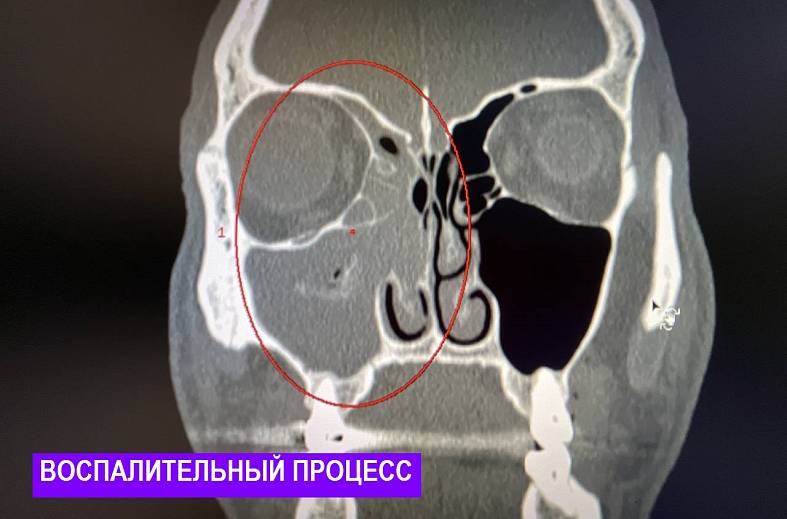

КТ-снимки хронического этмоидита: подробная визуализация

Раздел: Фотодневник открытий